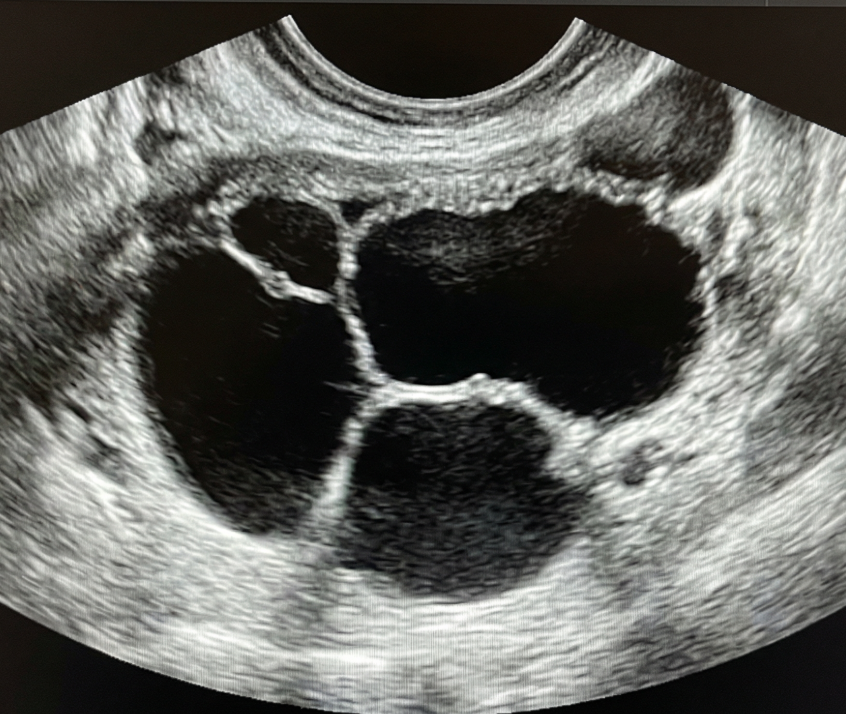

Risco: <10%Cisto unilocular ≥ 10 cm, cistos dermoides/endometriomas/hemorrágicos ≥ 10 cm, cisto unilocular com parede irregular < 3 mm, cisto multilocular < 10 cm com parede lisa, lesão sólida com superfície lisa.

Achados ultrassonográficos

Se não removida cirurgicamente, considerar seguimento com US em 6 meses. Se sólido considerar US com especialista (se disponível) ou RM (com classificação O-RADS MRI). Seguimento com ginecologista.